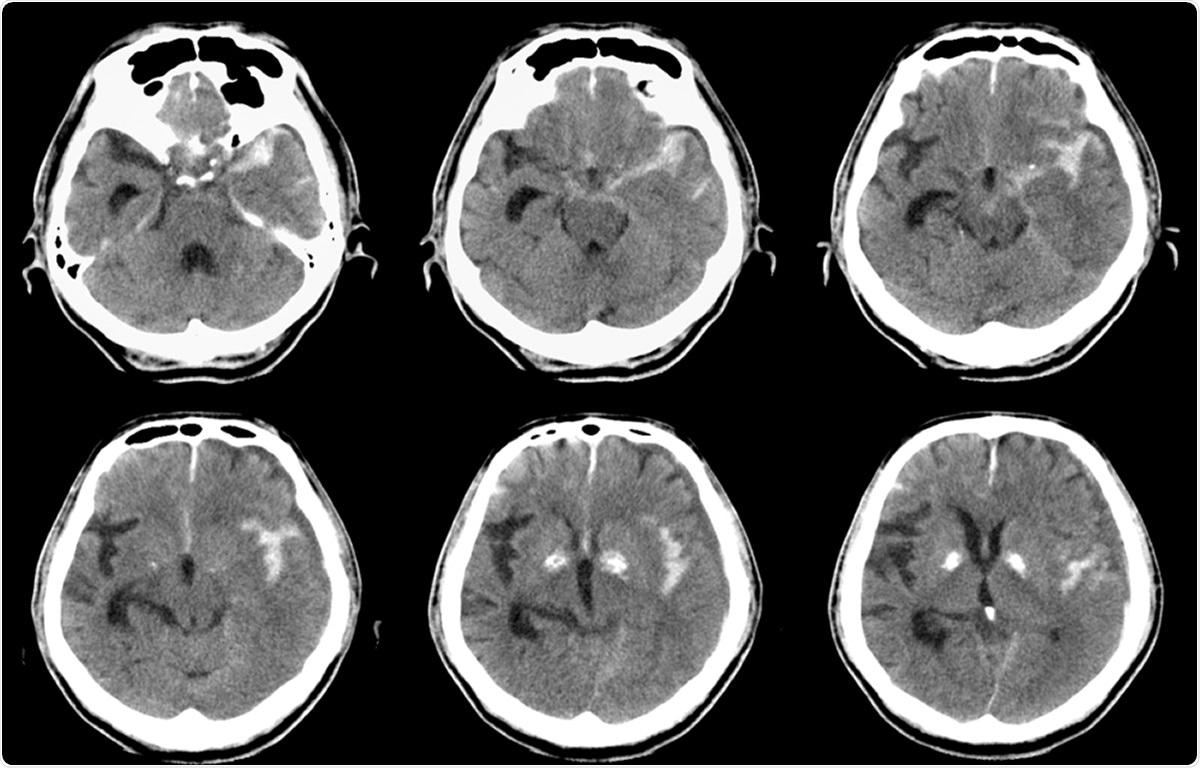

Computed tomography (CT) of brain : Left SAH (Subarachnoid hemorrhage). Image Credit: MossStudio / Shutterstock